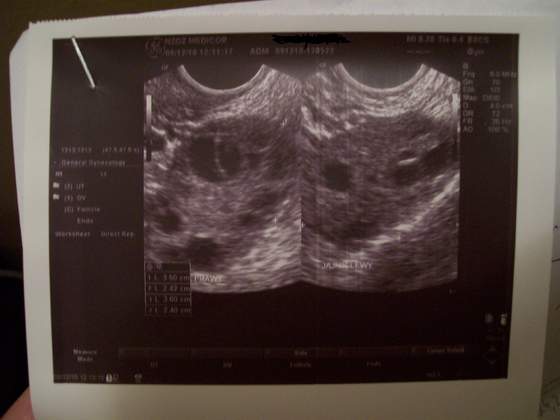

A to moje jajniki i podzielony pecherzy po lewej i co o tym sadzicie?

Załączniki

• usg.jpg

usg.jpg

18,3 KB · Wyświetleń: 74